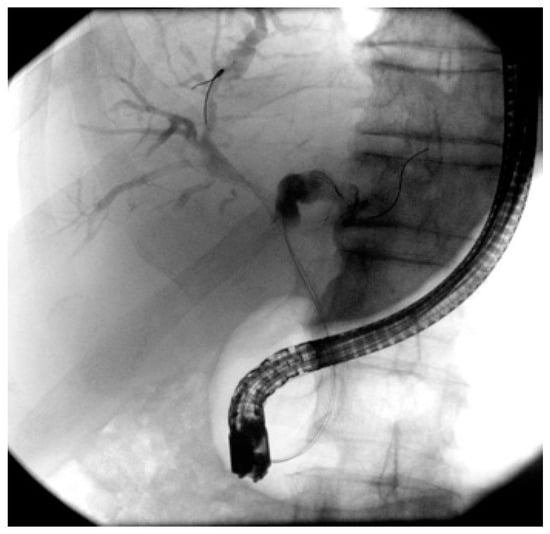

4.2. ERCP in Perihilar Strictures

- De Oliveira, P.V.A.G.; de Moura, D.T.H.; Ribeiro, I.B.; Bazarbashi, A.N.; Franzini, T.A.P.; dos Santos, M.E.L.; Bernardo, W.M.; de Moura, E.G.H. Efficacy of digital single-operator cholangioscopy in the visual interpretation of indeterminate biliary strictures: A systematic review and meta-analysis. Surg. Endosc. 2020, 34, 3321–3329. [Google Scholar] [CrossRef] [PubMed]

- Xia, M.X.; Pan, Y.L.; Cai, X.B.; Wu, J.; Gao, D.; Ye, X.; Wang, T.; Hu, B. Comparison of endoscopic bilateral metal stent drainage with plastic stents in the palliation of unresectable hilar biliary malignant strictures: Large multicenter study. Dig. Endosc. 2021, 33, 179–189. [Google Scholar] [CrossRef]

- Kim, J.Y.; Lee, S.G.; Kang, D.; Lee, D.K.; Park, J.K.; Lee, K.T.; Lee, J.K.; Lee, K.H. The Comparison of Endoscopic Biliary Drainage in Malignant Hilar Obstruction by Cholangiocarcinoma: Bilateral Metal Stents versus Multiple Plastic Stents. Gut Liver 2021, 15, 922–929. [Google Scholar] [CrossRef] [PubMed]